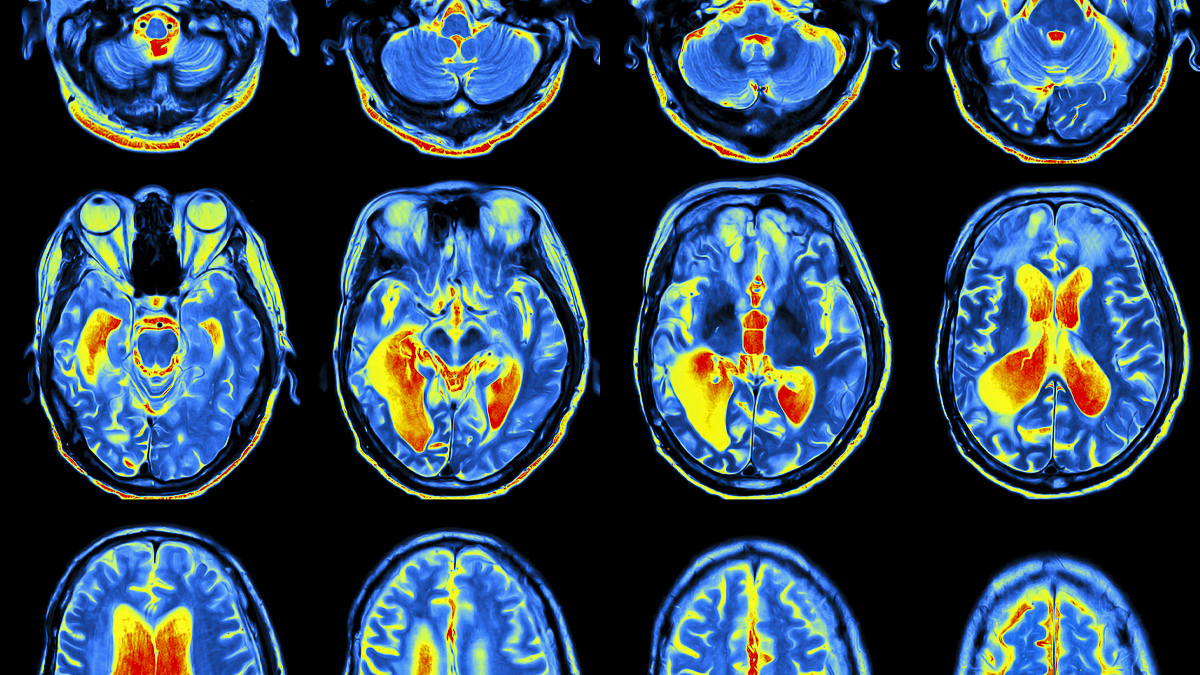

Research in Mathematical Biology covers two main themes - Systems Biology, Medicine, Neuroscience and Pharmacology, and Food, Supply Chains & the Environment.